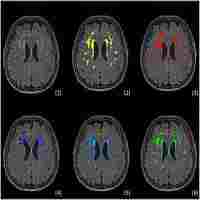

| Abstract | Automatic segmentation of white matter hyperintensities (WMH) from T2-Weighted and FLAIR MRI is a common task that needs to be performed in the analysis of many different diseases. A method to segment the WMH is proposed whereby a local intensity model (LIM) of normal tissue is generated. WMH are detected as outliers from this model. The LIM enables an accurate modeling of intensity variations thus reducing false positives. Moreover only scans with normal tissues are required to create the model. Twelve normal scans were used to generate the LIM and validation was conducted on a set of 46 scans. Similarity indices between the proposed approach and manual segmentations were 0.59±0.15, 0.65±0.08 and 0.77±0.08 for subjects with small, moderate and large volume of lesions respectively. The proposed approach performed better than support vector machines on the same dataset and compared favorably to approaches in literature. |